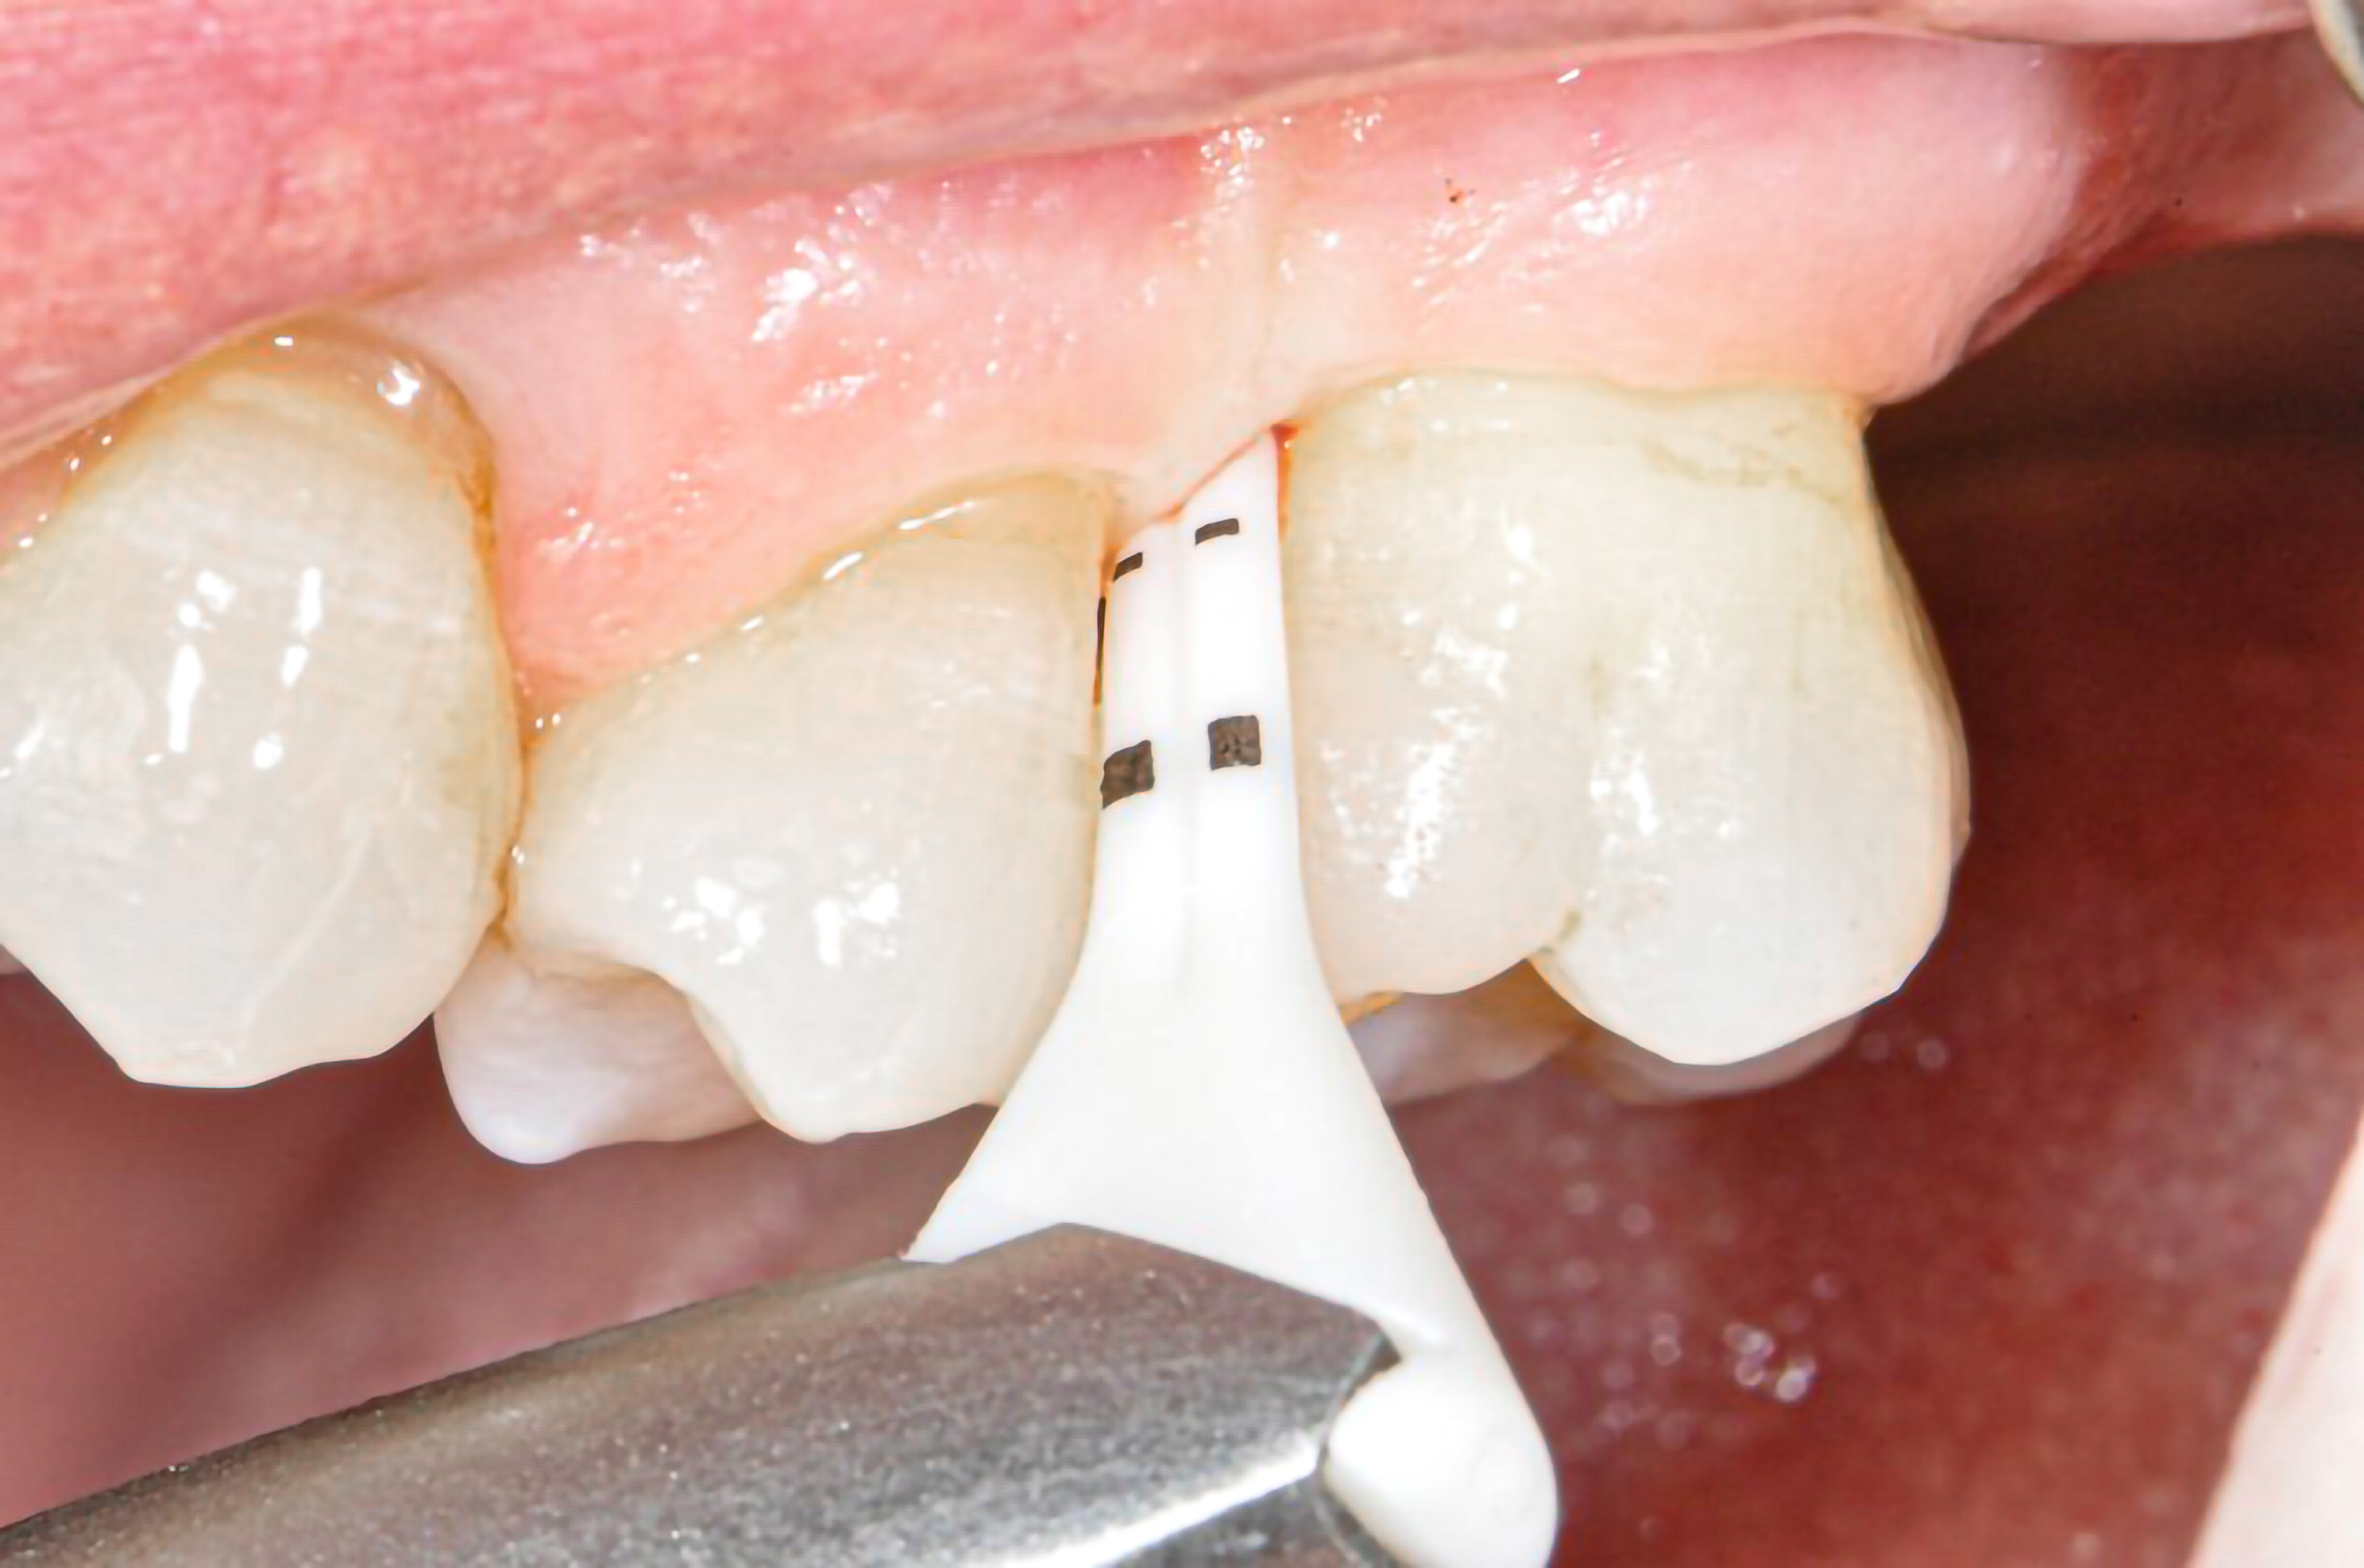

Bezüglich Methoden für das supragingivale Biofilm-Management wurden für spezielle Luft-Wasser-Pulver-Systeme („Airflowing“) im Vergleich zum konventionellen Vorgehen mit rotierenden Bürstchen und Pasten („Politur“) gleichwertige oder bessere klinische Ergebnisse gezeigt (27-29). Mit einem systematischen, modularen Protokoll für die primäre („PZR“) und sekundäre (AIT, UPT) professionelle Prophylaxe wird nach Spülen mit antiinfektiver Lösung und Befundaufnahme (Schritt 1), obligatorischem Anfärben und Patienteninstruktion (Schritt 2, Abb. 2) zunächst der Biofilm mit speziellen Luft-Wasser-Pulver-Systemen und dann erst verbleibender Zahnstein mit piezokeramischem Ultraschall entfernt (Schritte 4 bis 6, Abb. 3-5). Die sauberen Zahnoberflächen können dann optimal untersucht und ein risiko-adaptiertes Recall-Intervall festgelegt werden (Schritte 7 und 8 der Guided Biofilm Therapy GBT, Abb. 6) (27).